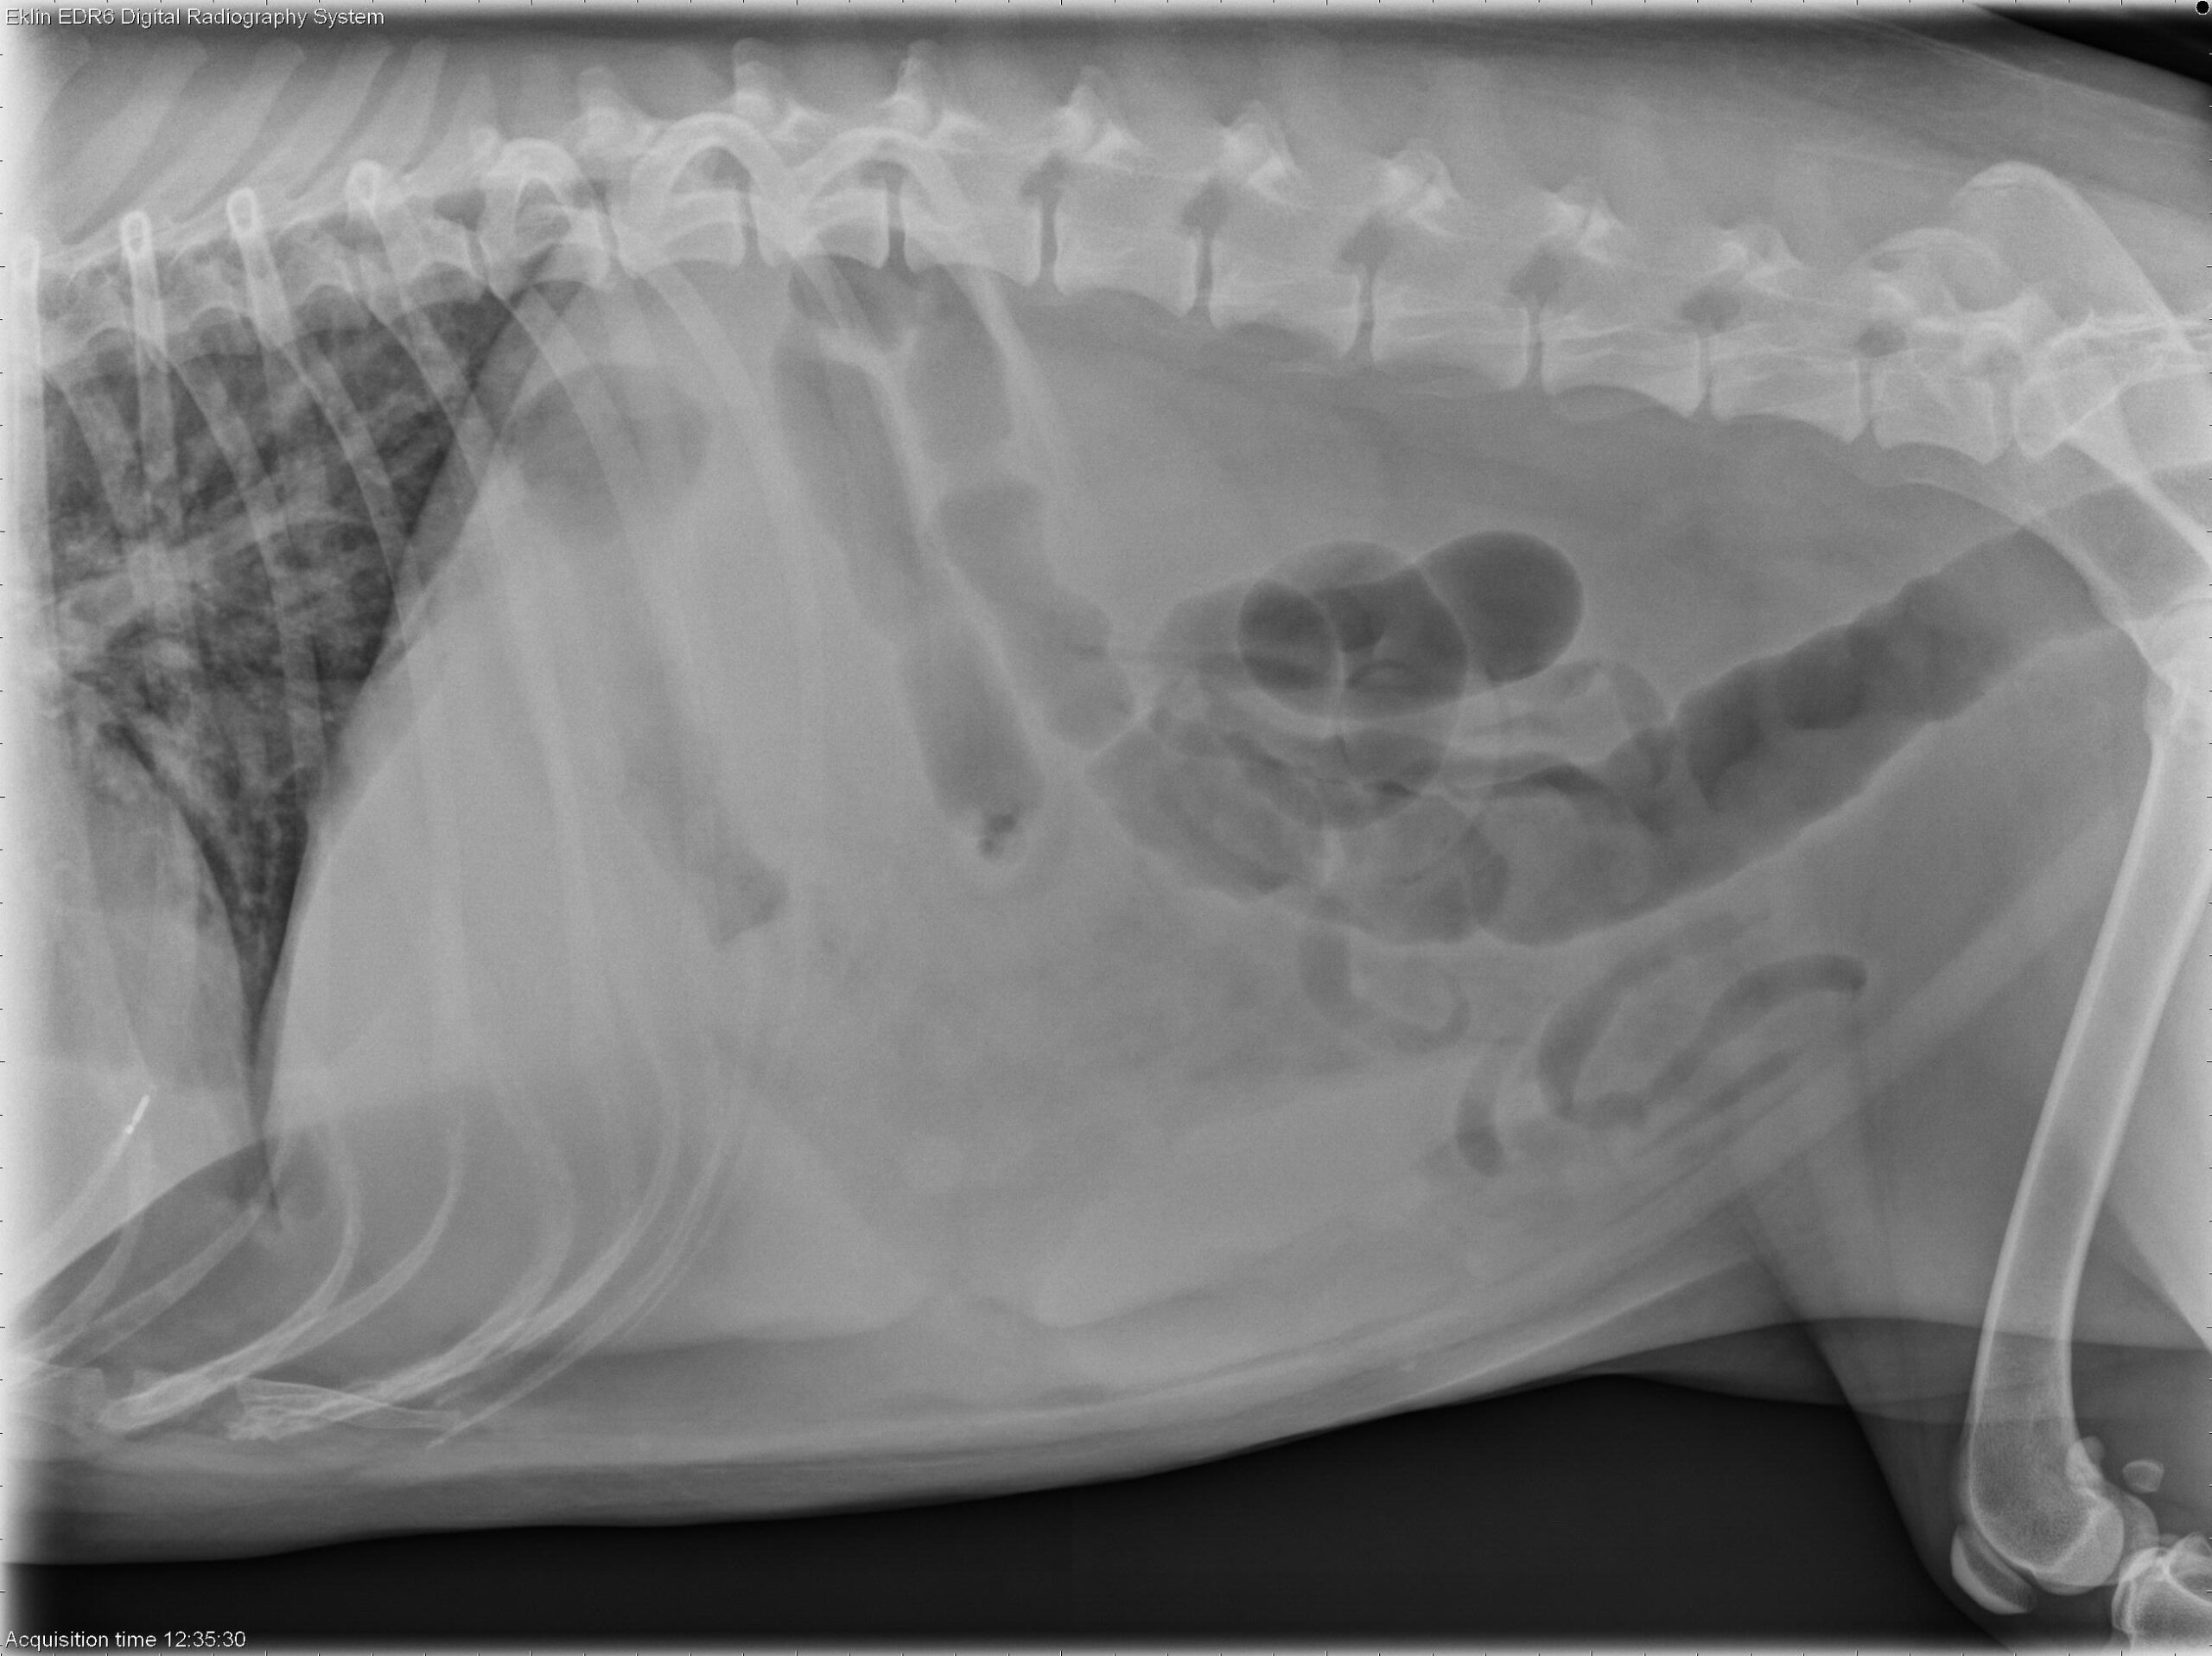

Below you’ll find the 4 X-ray images of the thorax. Use the arrows to scroll through, or click on the image to enlarge.

Thorax: There is increased soft tissue opacity within the pleural space, with retraction of the lung lobes and partial silhouetting with the cardiac silhouette, consistent with pleural effusion. A patchy broncho-interstitial pattern is present in the lungs. The cardiovascular structures appear normal.

Abdomen: The abdomen is distended with poor peritoneal detail. The liver and spleen are enlarged with rounded margins. The colon is moderately distended with gas. The small intestines appear normal. The urinary tract is poorly visualized.